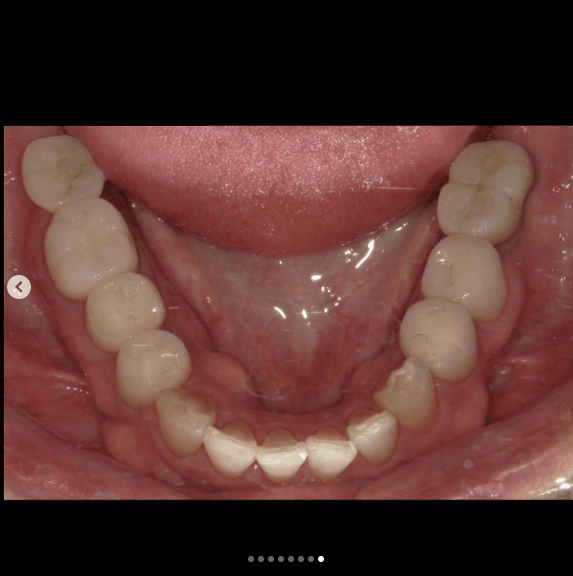

歯が欠けていて、隙間がある。

歯並びが気になる。

亀裂が入っている。

歯の無いところがある。

見える銀歯が気になる。

綺麗な口元になりたい。

という患者様の診療です。

上はジルコニアセラミックでかけているところを修復しながら、綺麗な歯並びで、患者様のお好きな白い歯に。

下の歯の無い所にはインプラント。

見える銀歯は外して綺麗な歯に修復。

また、ホワイトニングをして上の歯との色のギャップを少なくして、明るい口元にしました。